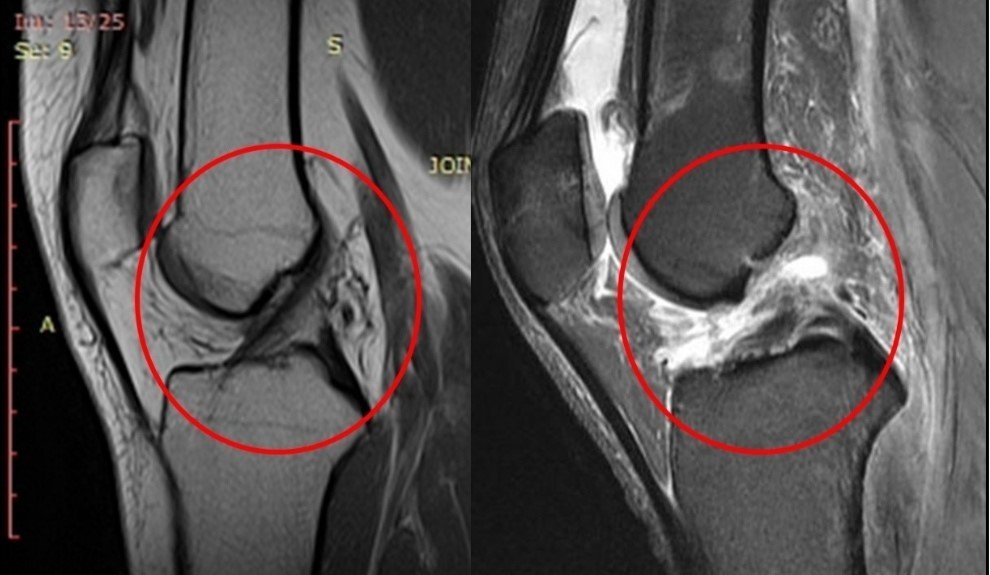

МРТ в діагностиці пошкоджень хрестоподібних зв'язок

Золотим стандартом як ми говорили вище є магнітно-резонансна томографія-даний метод має високу точність діагностики, що дає змогу уникнути непотрібної артроскопії.